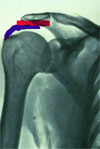

Schemat : na niebiesko przyczep m. nadgrzebieniowego, nad nim na czerwono kaletka maziowa podbarkowa (bursa subacromialis) z bezpośrednim kontaktem z wyrostkiem barkowym. Kaletka podbarkowa eliminuje / redukuje  tarcie.